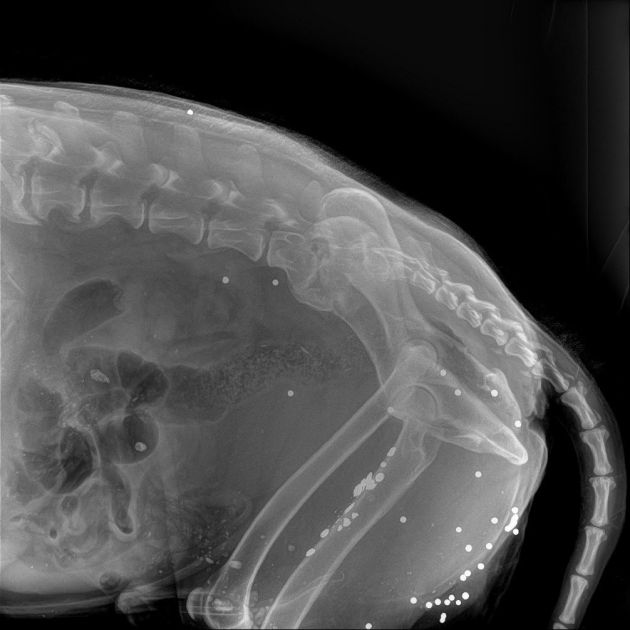

Животное доставили в ветклинику в Красное Село. Как рассказал 47news директор фонда Сергей Лучинский, при обследовании выяснилось, что в собаку стреляли. Рентген показал больше 30 шариков, крайне похожих на ружейную дробь. Раны есть даже на голове. Кроме того, волонтеры предполагают, что собаку мог сбить автомобиль.